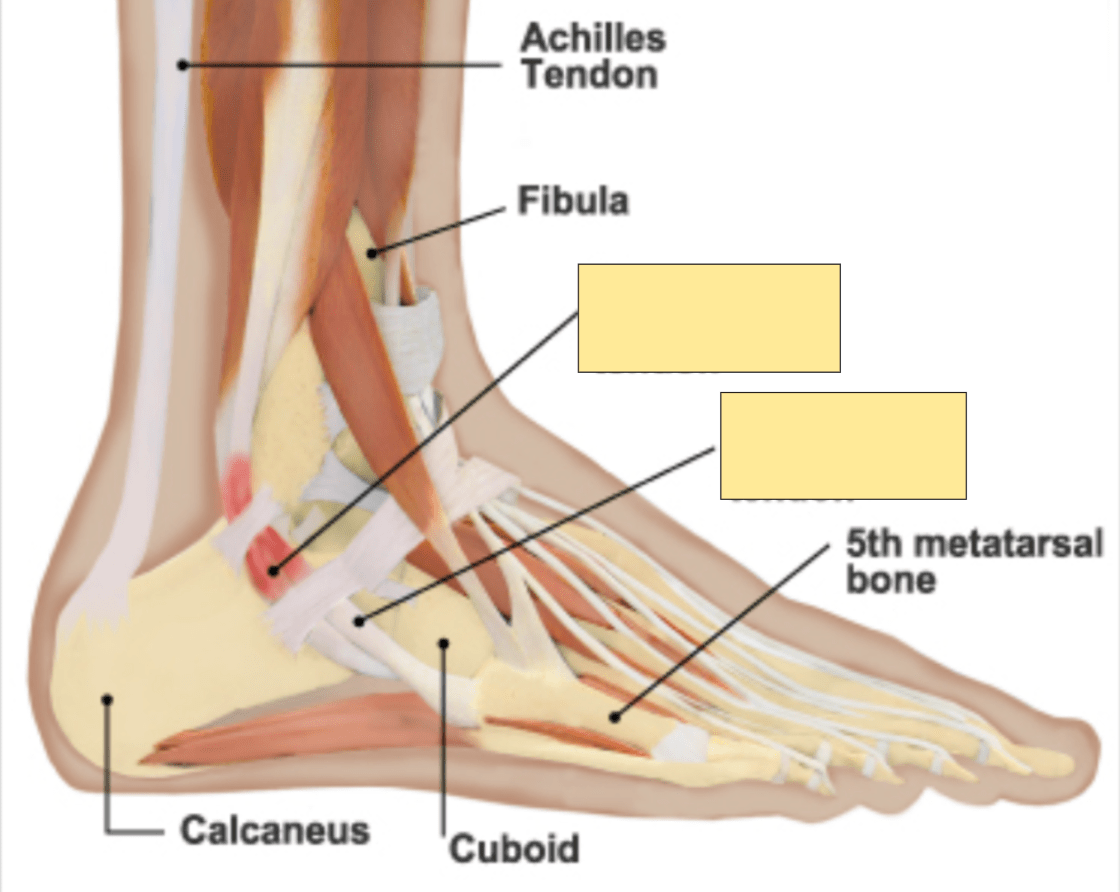

What structure is marked with dark arrowheads.

What is ATFL?

What is CFL?